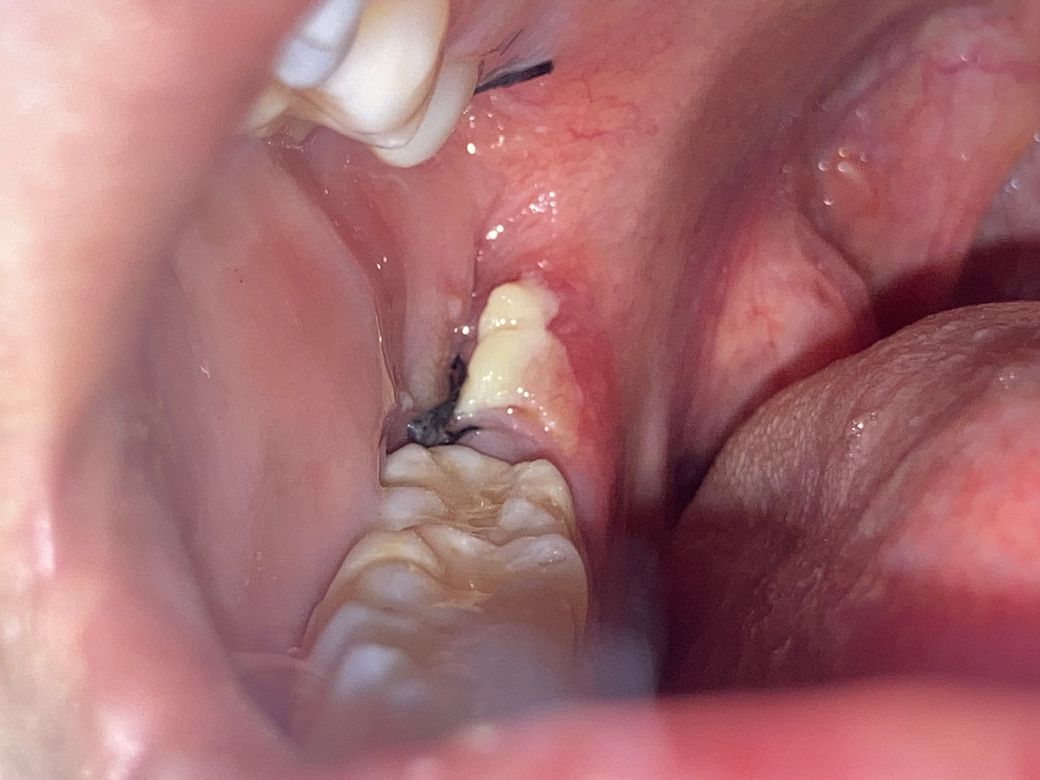

사랑니 발치 3일. 하얀덩어리의 정체?

이게 뭔지 알 수 있을까요 ㅜㅜ 위아래 동시에 뽑앗는데 아래에만 생겼어요 혹시 몰라서 제거 안했고 가글 열심히 했어요 약도 잘 챙겨먹구요 ㅜㅜ 다른 아빨 뺏을때는 이러지 않았어요

• 1번 째 사진

사랑니를 뽑는 과정에서 연조직에 자극이 되었다면 해당 부위가 하얗게 가피처럼 생성될 수 있습니다.

통증이 있거나 냄새가 나지 않는다면 큰 문제가 되지 않을 것으로 생각되지만 걱정이 된다면 치과에서 진료를 받아 보는 것이 좋습니다.

하얀색 막은 상피세포가 차오를 때 생기는 막입니다. 통증이 심하거나 악취가 나지 않으면 잘 나을겁니다.

지혈제가 아니라면 음식물같습니다. 일단은 치과에 가셔서 소독을 한번 받아보시는게 좋을것같습니다.